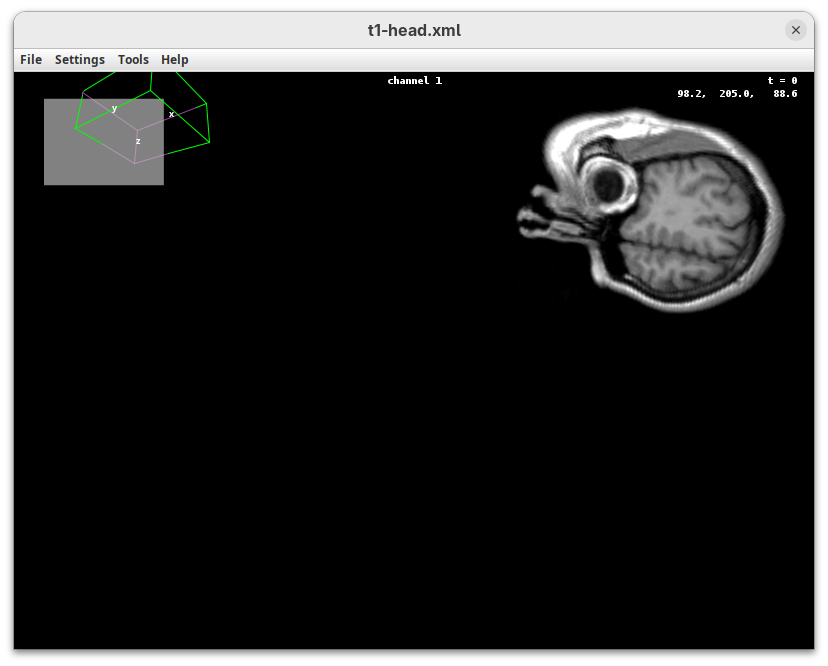

BigDataViewer (Pietzsch et al. 2015) is one of the most important tools for visualizing large, multidimensional datasets. It provides a simple and intuitive interface and shortcuts to swiftly navigate through your sample even on a regular laptop. This is possible because of the underlying file format used by BigDataViewer: the XML/HDF5 combo. Therefore, before opening the plugin, we must convert our dataset.

The BigDataViewer interface will open showing an optical section of the head sample.

Getting familiar with BigDataViewer is an essential skill for navigating large 3D datasets. It’ll also be important for the multiview registration pipeline. So, take the time to learn the basic commands and shortcuts. It is nicely intuitive. The BigDataViewer’s page on the ImageJ Docs has the official documentation and we can also go to Help > Show Help for an up-to-date overview.

Some of the movements to try:

Left-click and drag: turn the sample around the mouse pointer at any arbitrary angle.Right-click and drag: move the sample in the XY plane (of the view).Scroll: move through the Z plane (of the view). UseShift+Scrollto move fast.Ctrl+Shift+Scroll: zoom in or out.

But, most importantly, are the commands to put your sample back to its original orientation or along any of the original dimension axes:

Shift+Z: orient the sample on the XY plane.Shift+X: orient the sample on the ZY plane.Shift+Y: orient the sample on the ZX plane.

Finally, a visual tip. The default interpolation between image slices is nearest-neighbors. Press I to activate the tri-linear interpolation to obtain a much smoother (and improved) data visualization.